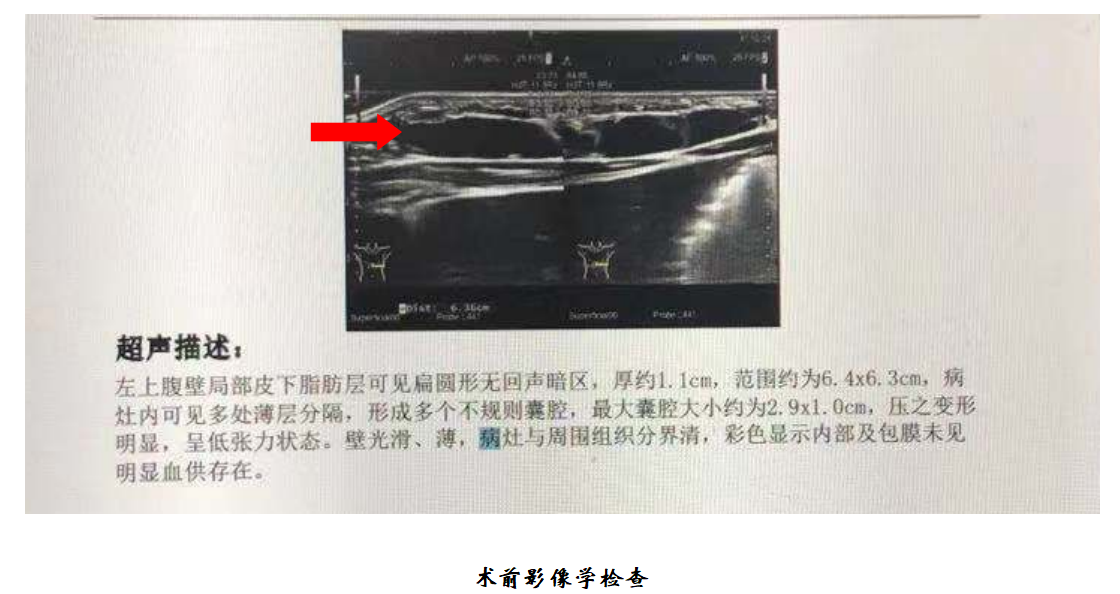

儿童腹壁淋巴管瘤介入微创治疗病例

【疾病类型】儿童腹壁淋巴管瘤

一、初识患者

患儿为2岁男童,因发现腹壁肿物就诊,近期肿胀明显,家长非常焦虑,不知道这是什么病,对治疗方案也一无所知,申主任看过患儿后,一边详细了解孩子病情和检查,一边安慰父母,告知父母这属于淋巴管瘤,需要尽早进行干预,目前多采用介入微创治疗,没有任何伤疤,之前采用手术治疗,瘢痕太大,现在不怎么用了。淋巴管瘤属于我们科室的常见病,我们已经治愈很多类似的患儿,告诉家长不要太担心,并给家长看了类似病人的成功治疗的案例照片。家长很快平静下来,也决心在这里完成手术。

二、手术过程

在安排的手术时间,家长如约住院,顺利完成术前准备,手术当天,患儿在全麻的过程中完成了手术,手术仅耗时半小时,术中无出血,手术过程非常顺利,术后孩子也没有任何不适,身上也没有任何伤疤。共住院3天,患儿平稳出院。

10. 淋巴管瘤怎么确诊?做什么检查?

根据病史和临床表现,淋巴管畸形的诊断并不困难。为了确定其部位、大小, 除常规检查外,可以采用彩超、磁共振等评估病变血供及范围。

淋巴管瘤影像引导经皮硬化(PSE)术主要是在超声及大型数字减影血管造影机 (DSA)引导下,用穿刺针精准穿刺病灶并抽尽液体,注射硬化剂,使瘤体在硬化剂的作用下逐渐消退。